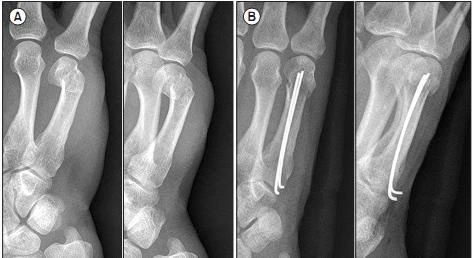

На снимке выше представлен случай смещенной антеградной интрамедуллярной фиксации перелома шейки пятой пястной кости правой руки.

(А) Рентгенологическое исследование перед операцией показывает: угол дорсально-шейной части пястной кости, сопровождающийся укорочением;

(B) Интраоперационная рентгеноскопическая рентгенограмма;

(В) Внешний вид движения мизинца через 2 недели после операции;

(D) Рентгенограмма через 8 недель после операции (из ссылки 6)